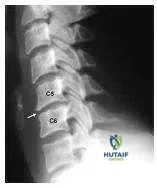

A 45-year-old man has neck pain following a motor vehicle accident. His neurologic examination is normal. His plain radiographs are shown (Slide). The most likely diagnosis is:

Correct Answer: Unilateral facet dislocation

Explanation:

The lateral radiograph shows translation and kyphosis at the level of injury. The facets of C4 do not superimpose on each to create a "double sail" sign. This patient has a unilateral facet dislocation. With unilateral facet dislocations, there is usually 3 mm to 4 mm of forward translation and 5° to 7° of angulation.